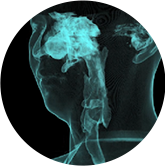

氣道

VR體繪制重建

氣道三維影像重建